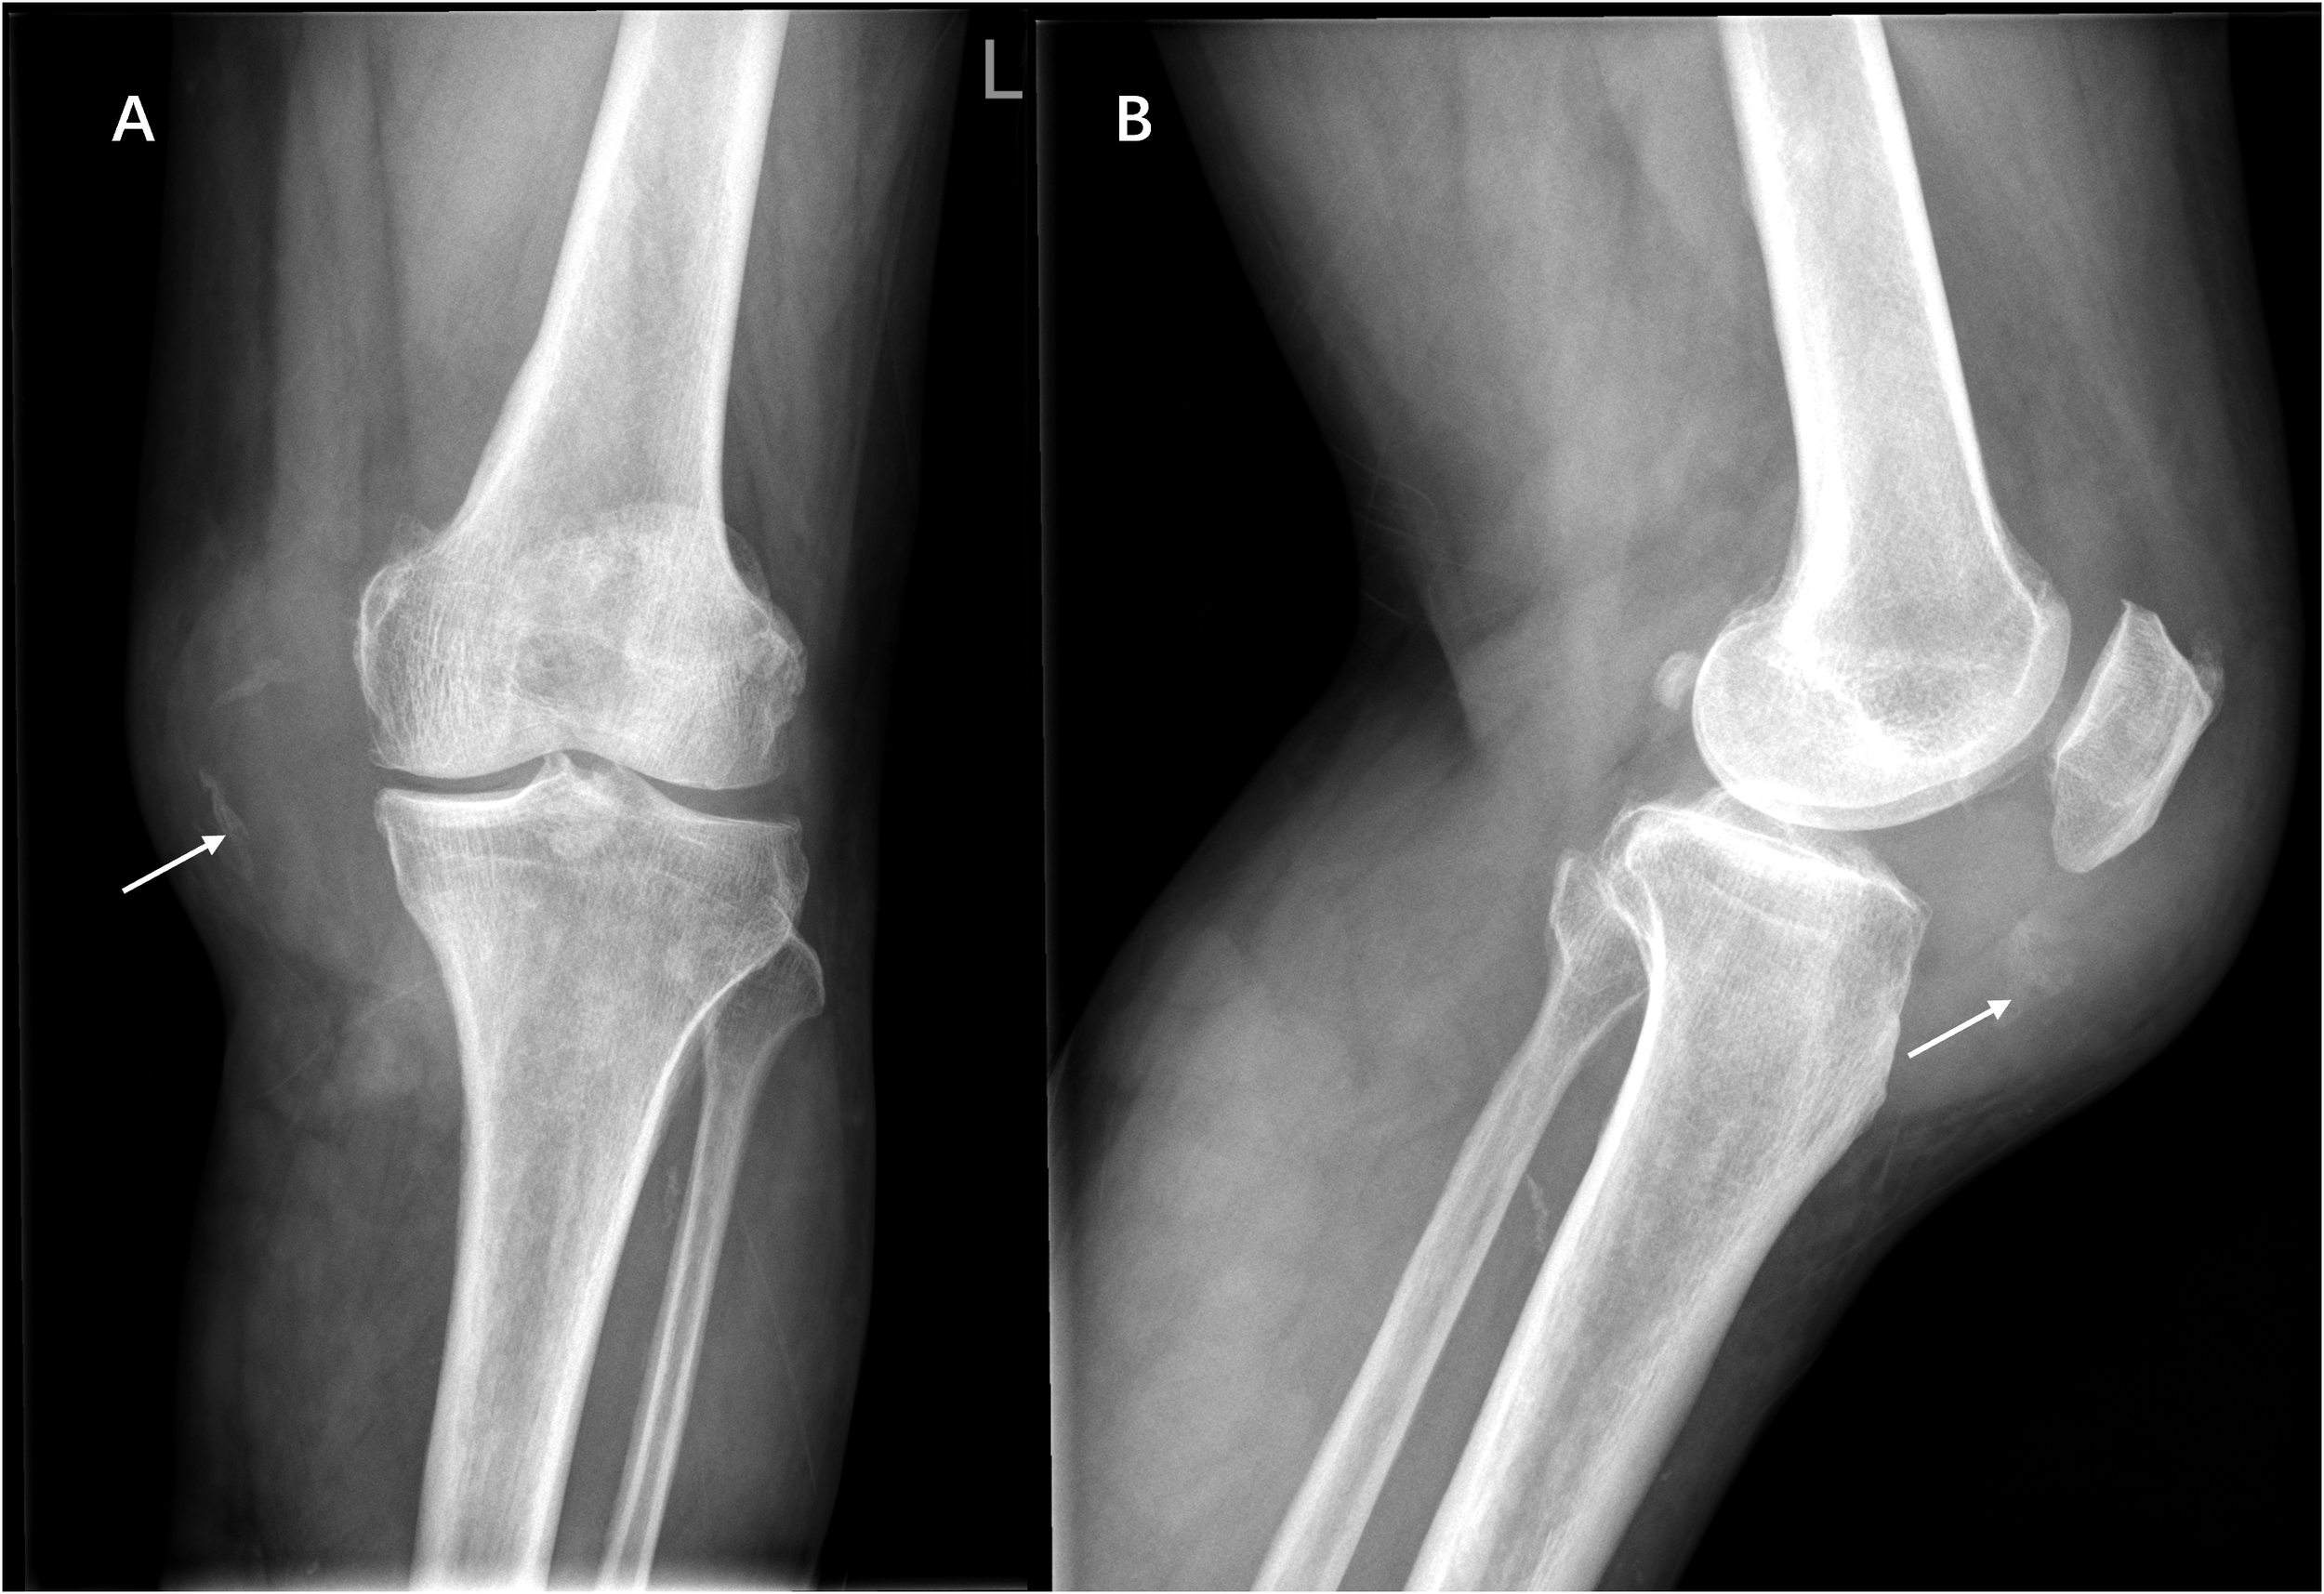

Figure 1

Anteroposterior (A) and lateral (B) radiographs showing marked swelling of the anteromedial soft tissue of the left knee with ill-defined borders and scattered calcifications within it (white arrow), without bone destruction.